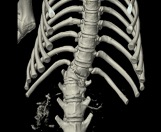

狗狗 車禍 骨盆骨折

狗狗的骨盆骨折相對於常見的四肢骨折 不容易單純靠xray 診斷及擬定手術計畫藉由電腦斷層影像的支援 能提高手術成功的機率

14kg 11歲的莓莓 術後10個月追蹤 行動自如一切正常喔

術前

術後

電腦斷層影像